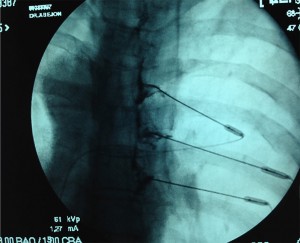

El punto de entrada se marca en el foramen que se visualiza debajo del pedículo, que sería el sitio de salida de la raíz. Se infiltra el punto de entrada con 5-10 ml de lidocaína al 1%. A través de este punto se avanza una aguja 22G de 10 cm, siempre en túnel visión. La aguja irá medial a la costilla y a la articulación costovertebral, y lateral al borde de la lámina.

Para confirmar la posición de la aguja se posiciona el arco de fluoroscopia rayo en lateral. Ésta debe alcanzar la región media o posterior del foramen en esta proyección.

Finalmente se rota el arco de fluoroscopia hasta la posición PA, la aguja no debe estar más medial de las 6:00 con respecto al pedículo. Se inyectan 1-2 ml de contraste para confirmar que la aguja está en la raíz , en la placa se debe observar la raíz dorsal y el espacio epidural.